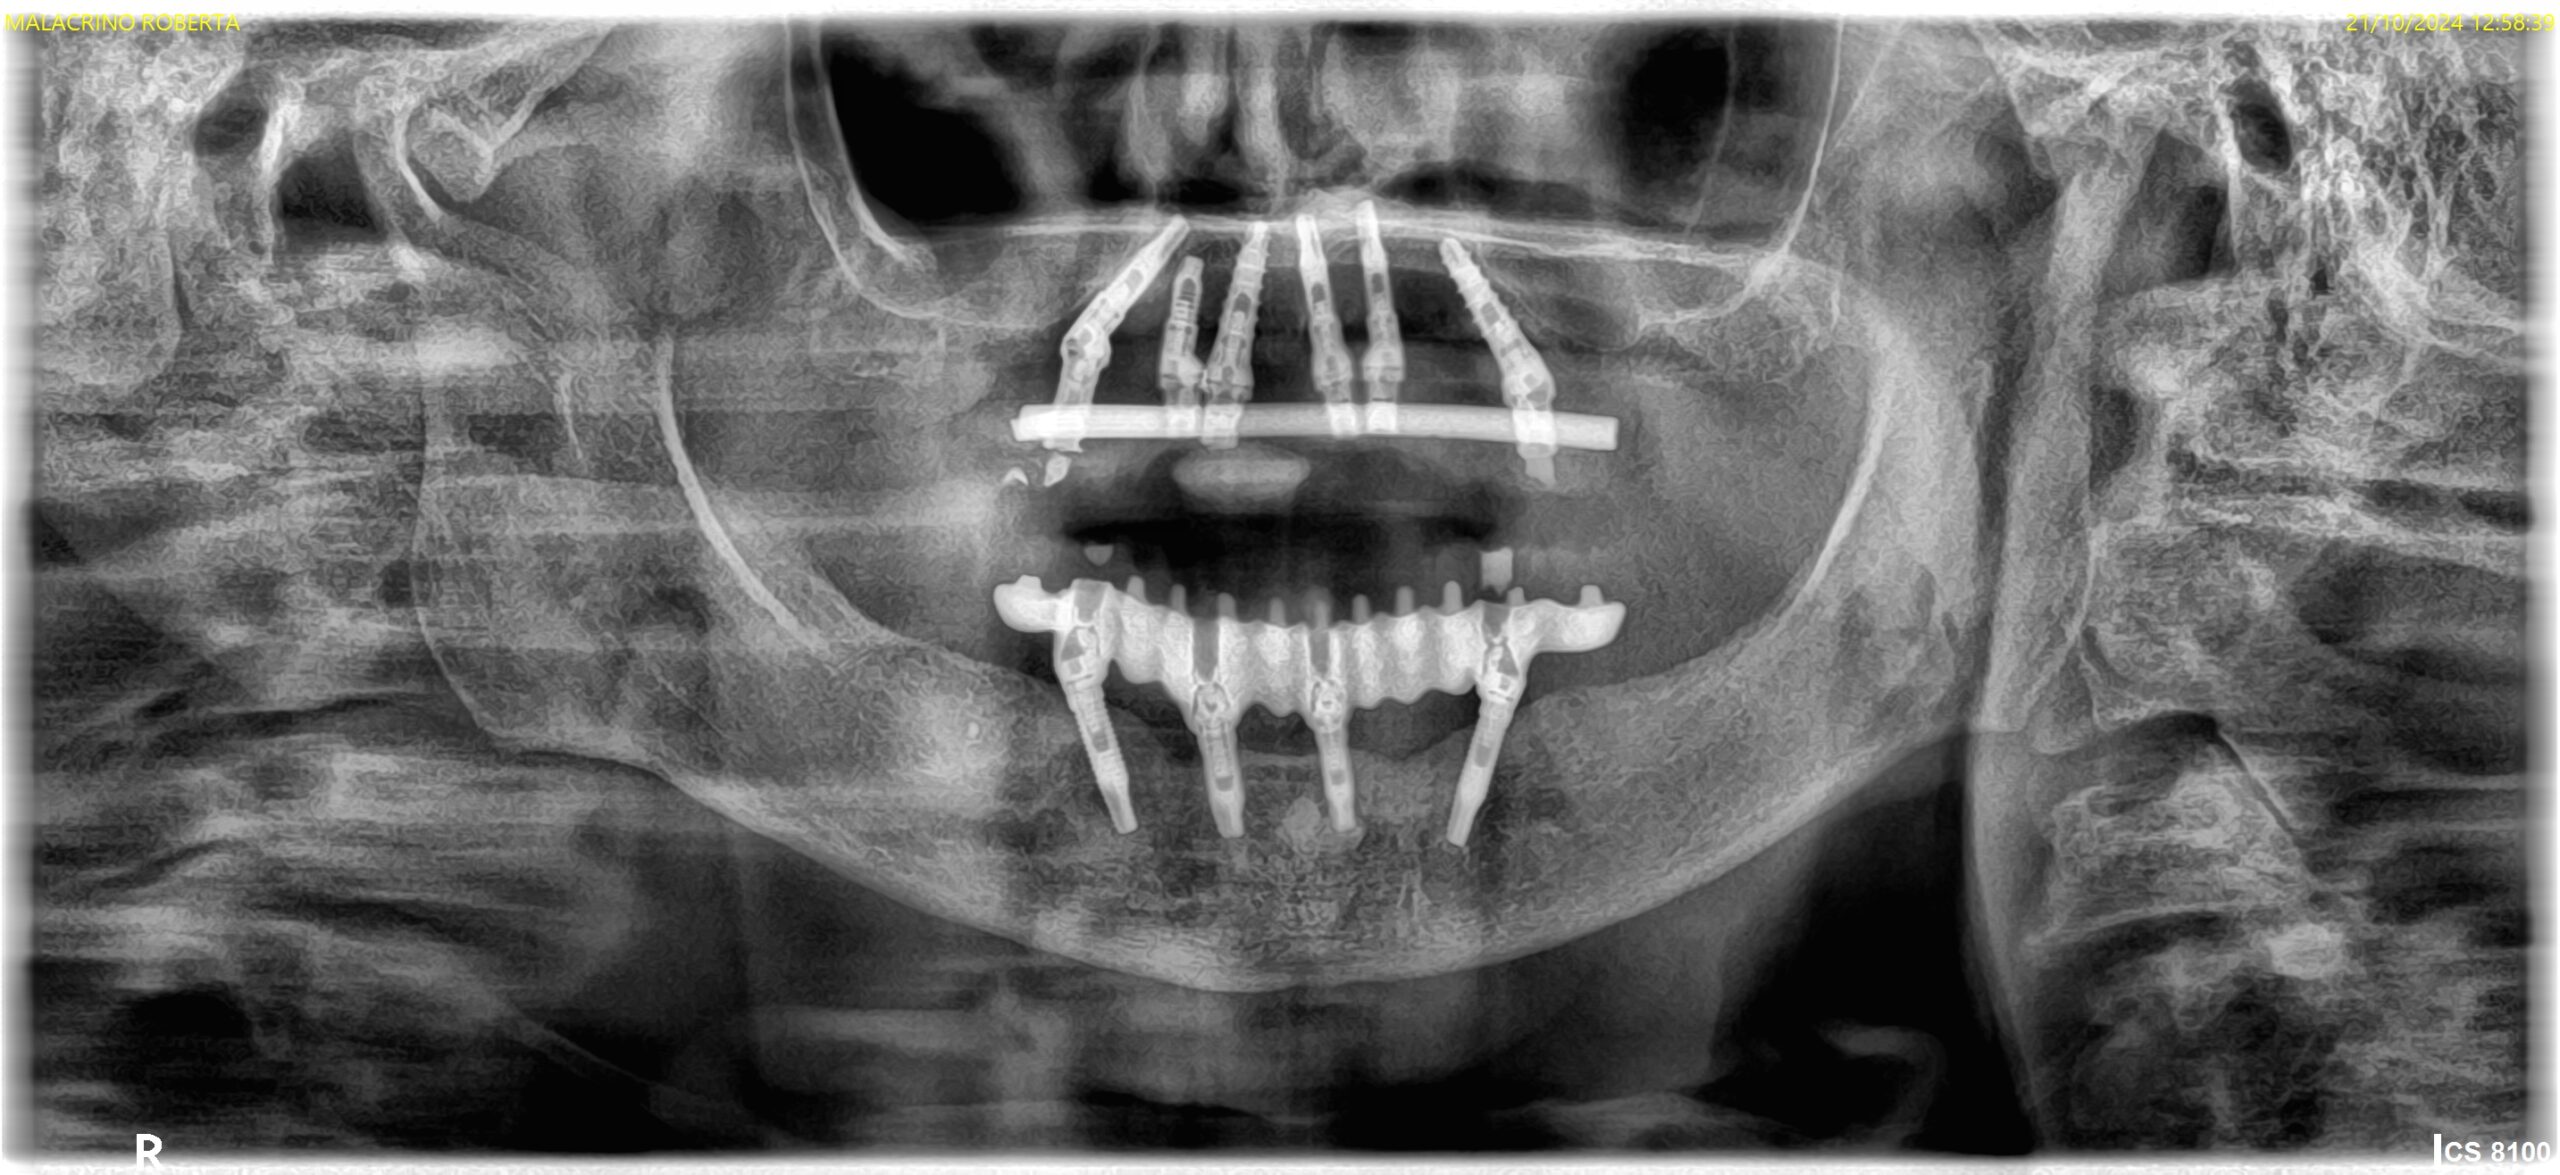

IMPLANTOLOGIA COMPUTER GUIDATA

Senza incisioni gengivali

Per l’inserimento di impianti osteointegrati, ci avvaliamo della tecnica di implantologia computer guidata BIOMAX™ che riduce notevolmente i disagi al paziente.

Infatti, questa tecnica prevede un’accurata fase di progettazione al computer che consente, nella maggior parte dei casi, di evitare fastidiose incisioni gengivali.